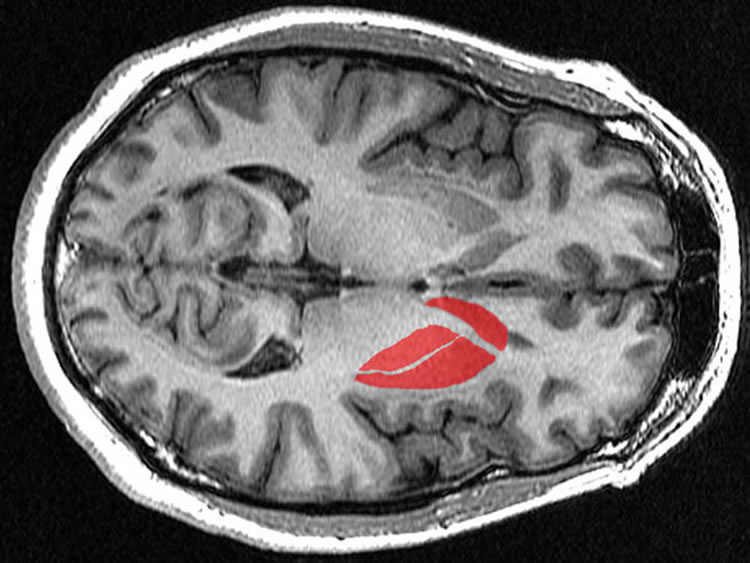

the location of the striatum

‘Compulsivity Circuit’ in Heavy Drinkers Identified

Researchers identify a driving network for compulsivity in those with alcohol use disorders. The study reports heavy drinkers have more activity in the prefronal cortex, insular and striatum, areas of the brain critical for reward and decision making.